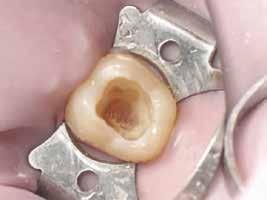

A gyökértömés elkészítése során meleg vertikális kompakciós technikát alkalmaztunk, sealerként pedig CeraSeal-t (Meta Biomed; 3. ábra) használtunk. A reszorbciós üreget Biodentine-nel (Septodont; 4. a–b ábra) töltöttük fel. A reszorbcióval érintett területtől koronális irányba elhelyezkedő csatornaszakaszt pedig tisztán meleg guttaperchával kezeltük. Ezt követően a lebenyszéleket visszafektettük, és varratok behelyezésével eredeti pozíciójuknak megfelelően rögzítettük. A koronai részt kompozit tömőanyag segítségével állítottuk helyre. Kontrollvizsgálatra 5, illetve 30 hónappal később került sor (5. ábra). A csontos telődés jelei már 5 hónap után észlelhetők voltak (6. a–c ábra). A 30 hónappal később végzett kontroll során sem találtunk csontban lévő lézióra, törésre vagy egyéb pathológiás elváltozásra utaló jeleket (7. a–b ábra)

A gyökértömés elkészítése során meleg vertikális kompakciós technikát alkalmaztunk, sealerként pedig AH Plus sealer-t (Dentsply Sirona) használtunk.

A reszorbciós üreget gyors kötési idejű

MTA-val (Mineral Trioxide Aggregate; Harvard Dental) töltöttük fel. A léziótól koronális irányban elhelyezkedő gyökércsatorna-szakaszt meleg guttaperchával zártuk, majd az MTA-val kitöltött üregre egy kis darab kollagénszivacsot helyeztünk és a lebenyt varratok segítségével eredeti pozíciójában rögzítettük (12. a–b; 13. a–b. ábra). A fog koronai részét Gradia kompozit tömőanyaggal állítottuk helyre (GC; 14. a–b; 15. ábra). Kontrollvizsgálatra két (16. a–b ábra) és négy évvel (17. a–b ábra) később került sor. A kontrollfelvételeken a bukkális kortikális jelenléte volt észlelhető. A fog körüli parodoncium egészséges volt, valamint a páciens sem számolt be tünetekről.

12. a–b ábra: A gyökértömés elkészítése.